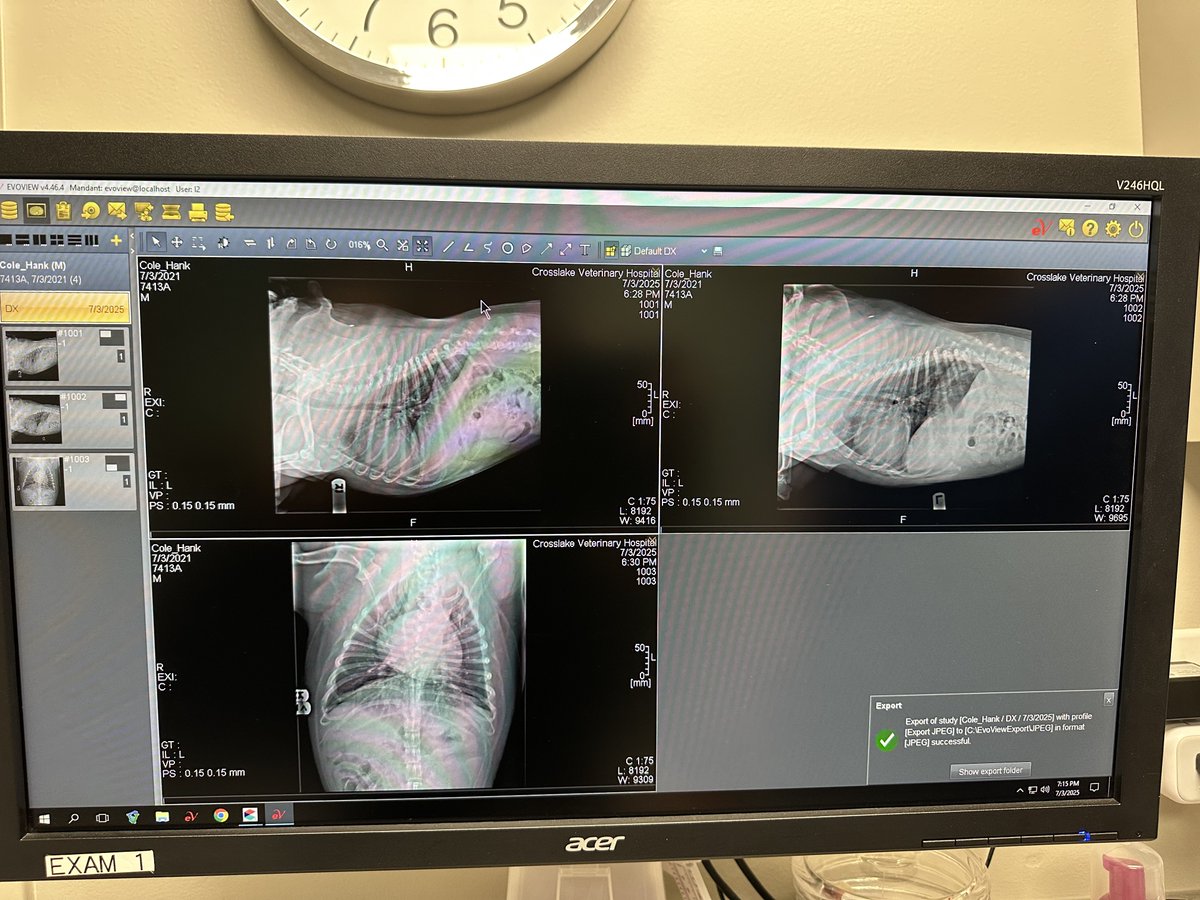

Update on Hank: took him in. They did lung X rays. Found some inflammation on the edge of one of his lungs or something from the water inhalation-  and gave him antibiotics to prevent further issues and potential pneumonia, so I guess it’s good that I took him in. The water was